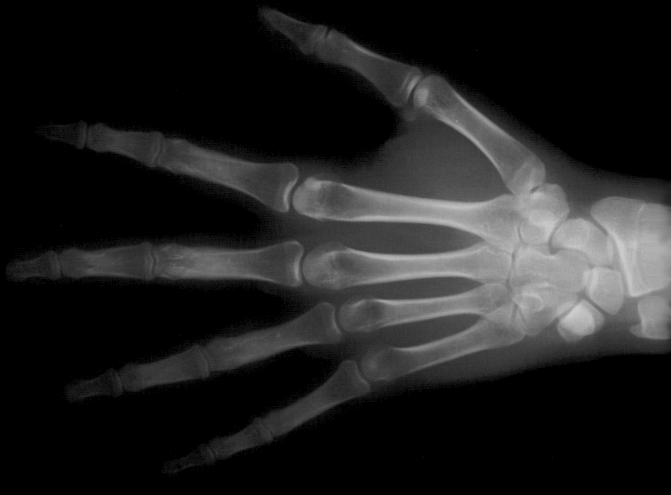

Radiografia della mano per la valutazione del grado di maturazione ossea